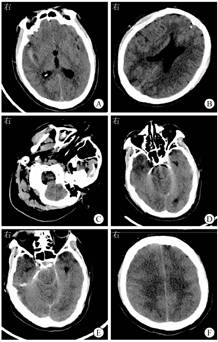

患者男,55岁,2021年9月14日因"头痛、发热2 d,意识模糊1 d"入江阴市人民医院。2021年9月12日患者出现头痛、发热,症状逐渐加重,伴全身乏力,9月13日至当地卫生院予以静脉滴注头孢呋辛(1.5 g,2次/d)和利巴韦林(0.5 g,2次/d)。补液结束后患者不能理解他人语言,且困倦明显。9月14日患者困倦较前加重,遂至江阴市人民医院就诊。患者有常年出差史,入院前2 d从山东省返回江阴市,发病前1周有在野外河流中游泳史,其余病史无特殊。入院体格检查:体温为38.9 ℃,心率为112次/min,呼吸为35次/min,血压为189/103 mmHg(1 mmHg=0.133 kPa)。神志模糊,格拉斯哥昏迷评分(Glasgow coma scale,GCS)为10分(E4V1M5),查体不配合,可自主睁眼,混合性失语,双侧瞳孔直径为2 mm,对光反应迟钝,双肺呼吸音清,未闻及明显干、湿啰音,心律齐,未及杂音,腹软,无肌紧张。四肢疼痛刺激可见自主活动,四肢肌张力不高,左侧巴宾斯基征可疑阳性,克尼格征(+),布鲁津斯基征(+),颈强直(+)。实验室检查:白细胞计数为6.60×109/L,中性粒细胞绝对值为5.10×109/L,中性粒细胞比例为0.937;尿常规示葡萄糖为(4+);空腹血糖为13.1 mmol/L,CRP为167.0 mg/L,降钙素原为1.07 μg/L,纤维蛋白(原)降解产物为33.9 mg/L,纤维蛋白原为5.73 g/L,D-二聚体为7.77 mg/L,抗凝血酶Ⅲ百分比为0.739, IL-1β为6.45 ng/L,IL-6为267.0 ng/L,TNF-α为13.3 ng/L,神经元特异性烯醇化酶为64.0 μg/L。入院后行腰椎穿刺术,术中可见黄色混浊脑脊液流出,呈米汤样,脑脊液压力>400 mmH2O(1 mmH2O=0.009 8 kPa),脑脊液未镜检,脑脊液常规检测及脑脊液墨汁染色示单个核细胞比例为0.269,多个核细胞比例为0.731,脑脊液蛋白定性检查(潘氏试验)为阳性,红细胞计数为6.0×109/L,白细胞计数为32.9×109/L,墨汁染色为阴性,脑脊液生物化学检测示葡萄糖为0.54 mmol/L,蛋白质为1.84 g/L。入院当日行头颅CT检查示右侧上颌窦霉菌性炎症可能(图1A),脑组织基本正常(图1B)。给予头孢曲松(2.0 g,1次/d)抗感染,更昔洛韦(0.25 g,2次/d)抗病毒,因患者情况迅速恶化,立即升级为广谱抗菌药物(美罗培南、万古霉素)抗感染,辅以镇痛镇静,亚冬眠疗法脑保护(氯丙嗪50 mg+异丙嗪50 mg+盐酸哌替啶100 mg,0.9%氯化钠溶液稀释至50 mL,每小时静脉泵入5 mL,冰毯物理降温,水温设置为4~10 ℃,体温设置为34~35 ℃),气管插管连接呼吸机辅助呼吸等治疗。患者病情进展极快,入院第2天复查头颅CT示右侧裂高密度影(图1C),经电子计算机断层扫描血管造影术(computed tomognelphyamgiog raphy,CTA)检查后排除脑血管出血,脑组织出现肿胀(图1D),复查CT示脑组织肿胀进一步加重,并发脑疝可能(图1E和图1F)。患者出现尿崩及神经源性休克,请神经外科会诊行脑室外引流,降低颅内压,并置入颅内压探头监测颅内压,术后复查CT示双侧大脑半球和小脑组织肿胀未见缓解。第3天外送脑脊液行宏基因组学第二代测序(metagenomic next-generation sequencing,mNGS),检出福氏纳格里阿米巴(Naegleria fowleri)序列(序列数为722 126)。鼻拭子涂片找到活动阿米巴滋养体,见图2。结合mNGS及鼻拭子涂片结果,诊断为福氏纳格里阿米巴引起的原发性阿米巴脑膜脑炎(primary amebic meningoencephalitis,PAM),立即请感染科会诊,给予两性霉素B 1.5 mg/(kg·d),经脑室引流管脑室内给药及联合静脉滴注利福平10 mg/(kg·d)治疗。给药过程中患者出现颅内高压(70 mmHg左右)、脑疝,自主呼吸消失,脑功能监护仪显示患者状态指数(patient safety index,PSI)持续监测为0,抑制率(suppression ratio)为100%,脑电活动差,脑室外引流无脑脊液引出,复查经颅多普勒超声提示颅内大动脉血流呈振荡血流改变,提示脑死亡,家属放弃治疗。

福氏纳格里阿米巴入脑后即迅速繁殖,表现为急性和暴发性出血性脑膜脑炎[3]。该病一般潜伏期为3~7 d,有时短至24 h[5],临床表现与结核性脑炎、化脓性脑炎相似,无特异性,早期表现为流感样症状,最突出的体征是明显的脑膜刺激征[6,7,8],但病情进展更快,1周内即可发展为脑疝甚至死亡[8]。本例患者入院前被误诊为上呼吸道感染,入院第2天出现脑疝,提示临床医师在遇到类似的病例时需要考虑福氏纳格里阿米巴感染引起的PAM。患者既往无糖尿病病史,但血糖、尿糖均高,结合后期出现尿崩,考虑为中枢神经系统受损导致,但具体机制尚不明确[9,10]。另外,患者CT表现为进行性脑水肿[11],右侧裂高密度影,后经CTA检查排除脑血管相关性疾病,考虑阿米巴引起脑实质出血性炎症导致继发性蛛网膜下腔出血,与陈宝建等[3]的报道类似。